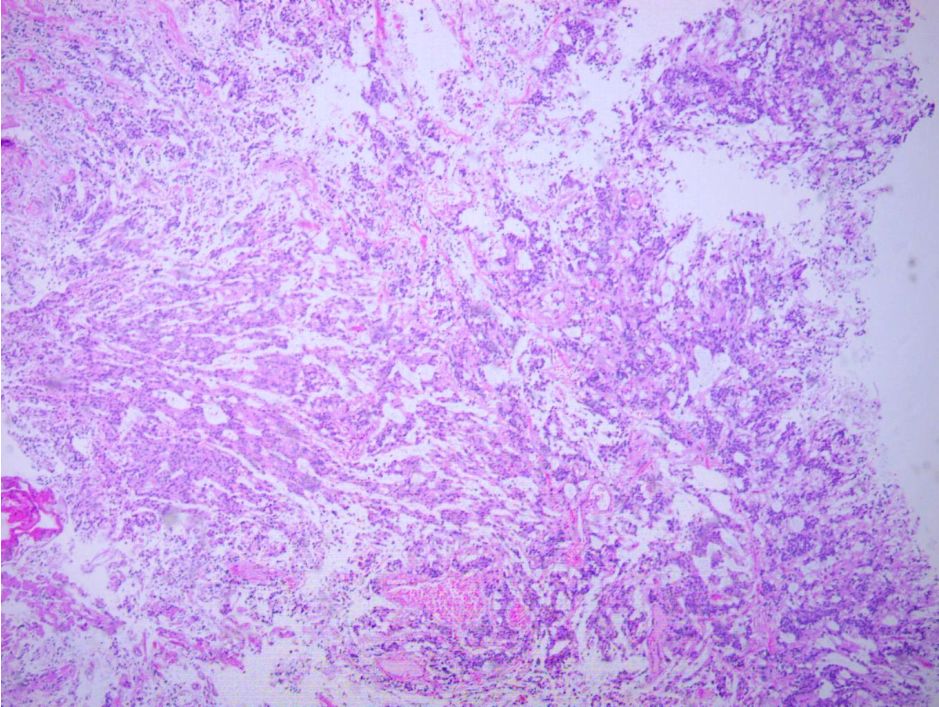

第二次术后病理与第一次相同(图6)。

图6. 第二次手术术后常规病理结果(2019-02-17):(椎管内)粘液乳头状室管膜瘤,WHO I 级。免疫组化结果:GFAP +,S-100 -,Vimentin +,CD99 +/-,CD56 +,CK (AE1/AE3) -,EMA -,Olig-2 -,P53 散在+,Ki-67 2-5%+。特殊染色结果:PAS -,Masson -,V.G染色 -。